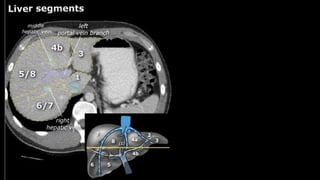

•Liver • A normalliver enhances homogeneously (irrespective of the scan phase). The liver receives about 80% of its blood through the portal vein (= nutrient-rich blood from the intestines). The remaining 20% is supplied by the hepatic artery. y is present, it is important to document its location. This may be crucial to any surgical options. Using the Couinaud classification, the liver is subdivided into eight individually functioning segments. Each segment has its own afferent hepatic artery and portal vein, and efferent hepatic vein and efferent bile ducts